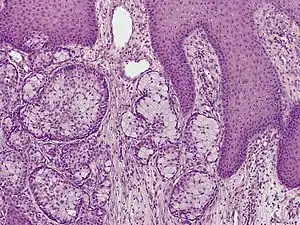

A skin biopsy is the common test used to diagnose Eccrine Carcinoma.[2] The biopsy will detect growth of new or abnormal tissue. Another test that can be performed is using Immunohistochemistry, but it is inconsistent.[2] Markers used to detect Eccrine Carcinoma consist of carcinoembryonic antigen, progesterone receptors, estrogen receptors, epithelial membrane antigen, pancytokeratins, and cytokeratin 7.[5][6]